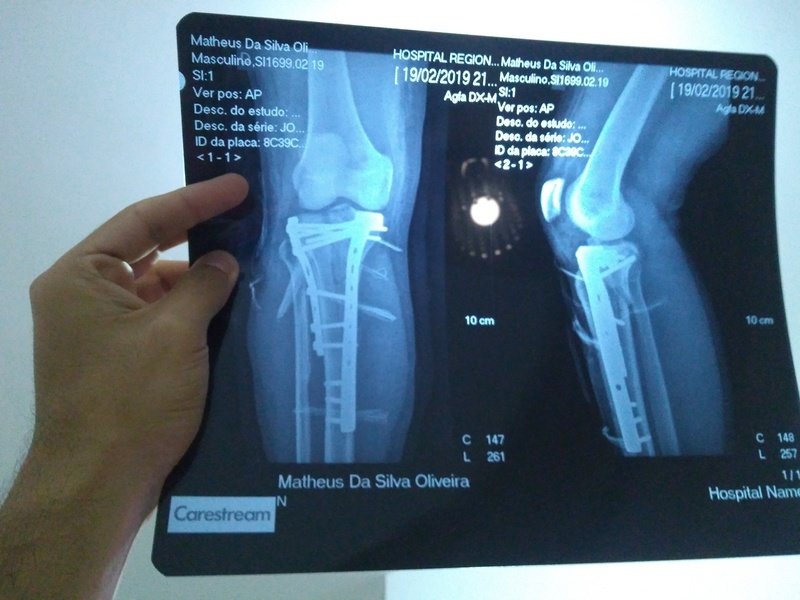

Meu sonho é ter esse volante pra jogar jogos de corrida. Porém me acidentei de moto durante o serviço, um cachorro entrou em minha frente e eu acabei fraturando a Tibia, um tombo muito bobo mas que tive que passar por cirurgia e colocar duas placas e 11 pinos, e por conta da demora do INSS tive que usar o dinheiro para outras finalidades(aluguel, contas de luz, alimentação). Qualquer quantia que puder ser doado já ficarei muito agradecido. Seria um presente de Natal mas se não conseguir até la vou estender o prazo um pouco mais.